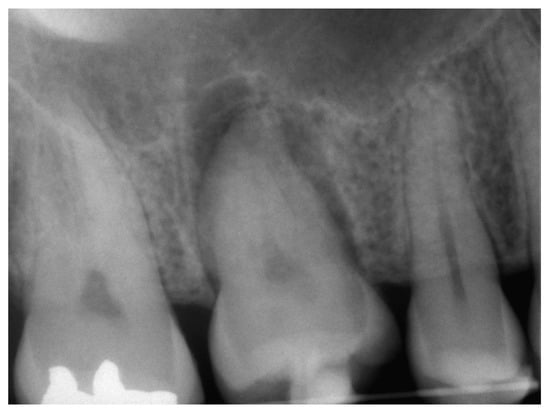

3.2. Case Report